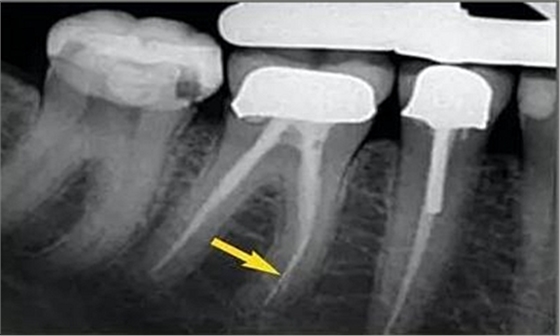

從近遠中向的X光片可以看出,在根尖三分之一區(qū)域,根管形態(tài)較寬而且彎曲。通過彎曲之后,單只銼沿直線到達根尖,沒有清理的根管的唇側(cè)部分。遺漏的區(qū)域在近遠中向的X光片中顯示得格外清晰。

唇面觀

近遠中觀